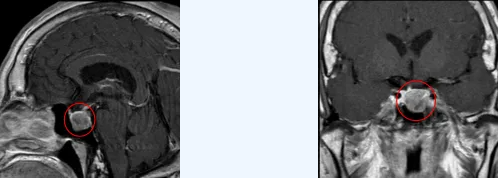

来到郑州大学第五附属医院后,神经外科三病区孟恩平副主任医师为她安排了详细检查。结果让人吃惊:生长激素高达21ng/mL,远超8ng/mL的正常值上限,MRI检查确认鞍区有占位病变。

“这不是正常的衰老,而是生长激素型垂体瘤引起的肢端肥大症。”孟恩平副主任医师解释。这个诊断意味着李奶奶身体的变化是肿瘤过度分泌生长激素所致。

垂体瘤大多为良性,根据大小可分为微腺瘤(<1cm)、大腺瘤(1-3cm)和巨大腺瘤(>3cm)。李奶奶所患的生长激素型垂体瘤就是其中一种类型,会导致肢端肥大症。